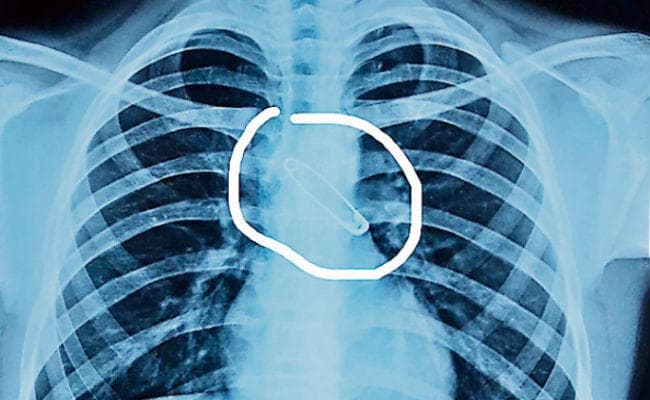

मुंह में सेफ्टी पिन दबाकर कार्टून देख रहा था बच्चा, खांसी आयी और सांस की नली में जा फंसा